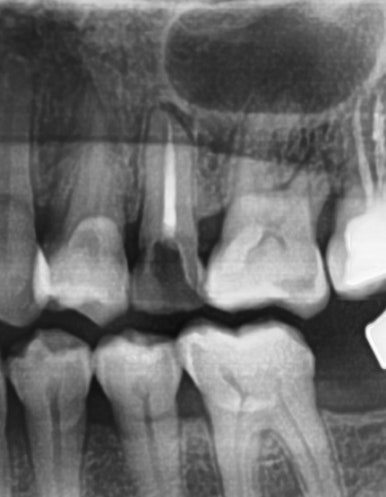

신경치료하고 크라운 안 한 치아->파절

신경치료하고 크라운 안 한 치아->파절이 흔합니다. 위 사진처럼 깎아서 크라운을 할 부위가 거의 없으면 잇몸위에다 크라운을 붙일 순 없겠죠. 발치가능성이 아주 커집니다.